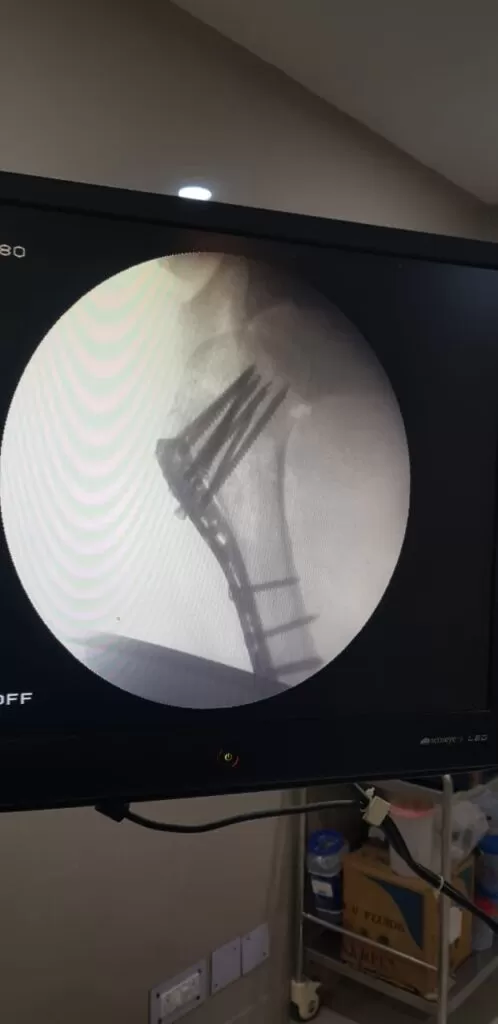

Mr. Akeel

Name: Mr. Akeel

Date of Operation: 10 Mar 2024

Age: 46 Years

Complex Trauma